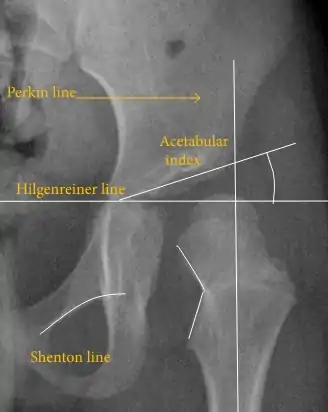

The most useful lines and angles that can be drawn in the pediatric pelvis assessing hip dysplasia are as follows:[3]

- (A) Hilgenreiner line, connects the inferior tips of the iliac bones,[4] at the triradiate cartilage. This line is used to measure the acetabular angle and as a reference for Perkin line.

- (B) Perkin line is perpendicular to Hilgenreiner line, touching the lateral margin of the acetabular roof.[5] This leads to four quadrants and a normal femoral head has to be located in the inferomedial quadrant. We can measure the lateral displacement of the femoral head with regard to the Perkin line by dividing the width of the head that crosses the Perkin line by the diameter of the head. The value for patients under 3 years must be 0 and in older children this ranges from 0 to 22%.

- (C) Shenton line is a continuous arc drawn from the inner edge of the femoral neck to the superior margin of the obturator foramen. In children over about 3 to 4 years of age, this line should be smooth and undisrupted, otherwise it may indicate a fracture or hip dysplasia.[6] However, in infants this line can be unreliable as it depends on the rotation of the hip when the image is taken.[7]

- (D) The acetabular index measures the acetabular roof slope. It is the most useful measure of acetabular dysplasia until 6 years of age. It is formed between Hilgenreiner line and the acetabular roof. In newborns, values of in males and in females are considered normal. It normally decreases with age: